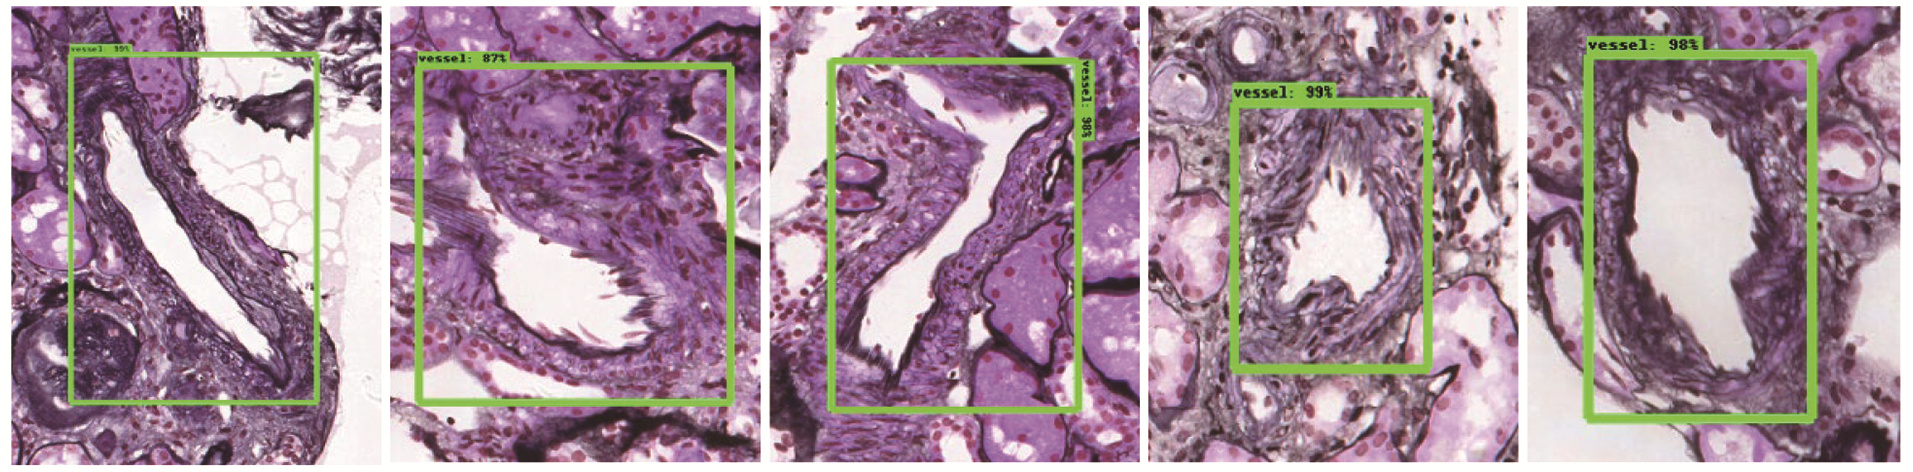

SALVI M, MOGETTA A, MEIBURGER K M, et al. Karpinski score under digital investigation: a fully automated segmentation algorithm to identify vascular and stromal injury of Donors'Kidneys. Electronics, 2020, 9(10): 1644.

BEVILACQUA V, PIETROLEONARDO N, TRIGGIANI V, et al. An innovative neural network framework to classify blood vessels and tubules based on Haralick features evaluated in histological images of kidney biopsy. Neurocomputing, 2017, 228, 143- 153.